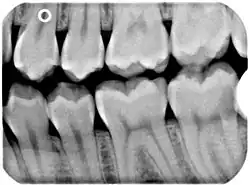

Bissflügelaufnahme links; Zahn 37 (unten rechts) lässt distal Karies erkennen